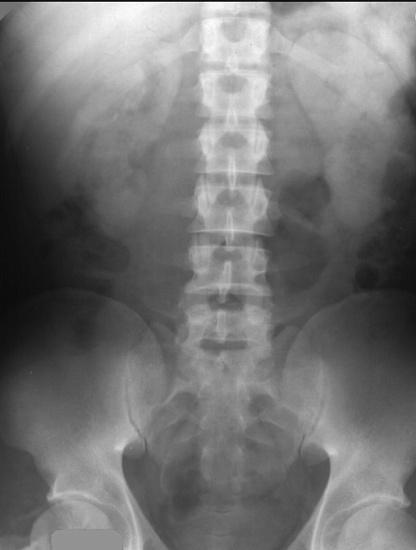

Рентгенография почек и мочевыводящих путей – важный метод визуализации почек, мочеточников и мочевого пузыря.

С помощью рентгенографии определяется положение почек, определяется наличие камней в мочевыделительной системе.

Внутривенная урография - метод диагностики аномалий строения почек и мочевыводящих путей, опухолей, кист, камней; оценки выделительная функция почек.